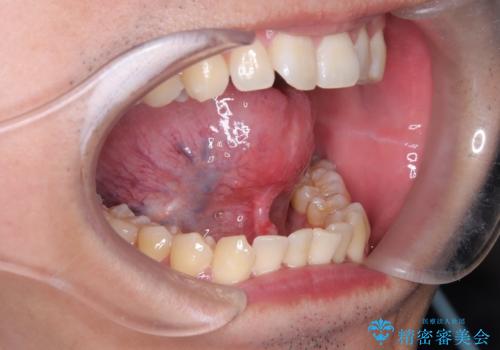

[舌小帯の形成術] 舌の動きが悪い 滑舌を改善したい!

担当医 大元洋佑